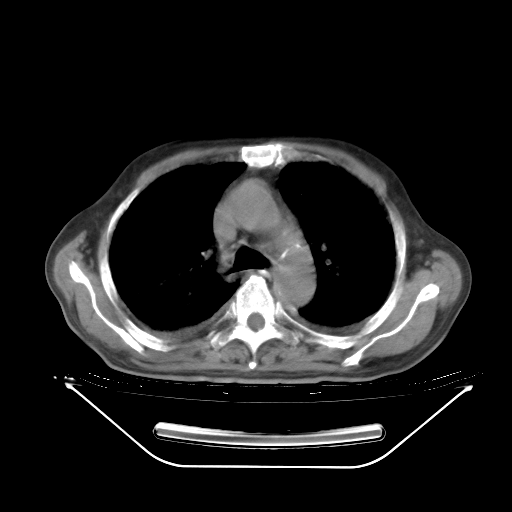

今天复查肺部CT,发现双肺广泛磨玻璃样改变。所以我把3月19日和5月9日相隔50天的肺部CT上传。请大家会诊。

5月9日肺部CT(在4月27日齐鲁医院肺部CT描述部分肺组织磨玻璃样改变,12天后肺组织广泛磨玻璃样改变)

2009年5月9日肺部CT

大致读了系列胸部CT:纵隔窗无明显异常,肺窗:从4、27至今:主要是双肺中下野外带可见毛玻璃样改变,目前处于急性肺泡炎阶段,至于原因考虑1、结替组织或胶原血管性疾病所致?2、恶性疾病如恶组在肺部所致的表现或细支气管肺泡癌?3、药物或其它原因如肺蛋白沉着症所致肺泡炎目前不太可能?总之,明天就去请我院的呼吸科、感染科、血液科和临免专家会诊哈。